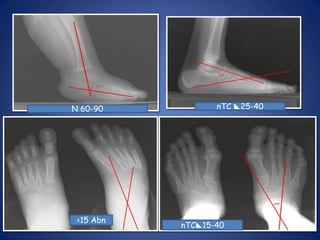

Radiological AssessmentTalo-calcaneal angle(AP) 15°-40

Talo-calcaneal angle (lat stress) 25-40 °

Talo-calcaneal index > 40 °

Tibio-calcaneal angle (stress lat) 5-15 °nTC25-40N 60-90<15 AbnnTC15-40

Tibio-calcaneal angle (stresslat) 5-15 °nTC25-40N 60-90<15 AbnnTC15-40